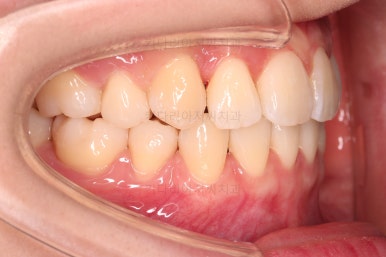

마찬가지로 초진 시 입안의 모습인데요.

전반적으로 약간 삐뚤지만 특히 윗니 앞니가 삐뚤고요.

송곳니는 덧니처럼 튀어나와 보이네요.

그리고 전반적으로 치아가 앞쪽으로 경사되어 있어서 앞니는 뻗친 느낌이 있네요.

가지런하게 하면서 앞니를 뒤로 당겨줘야 여러 가지 문제점들이 개선되기 때문에 발치교정을 했어요.